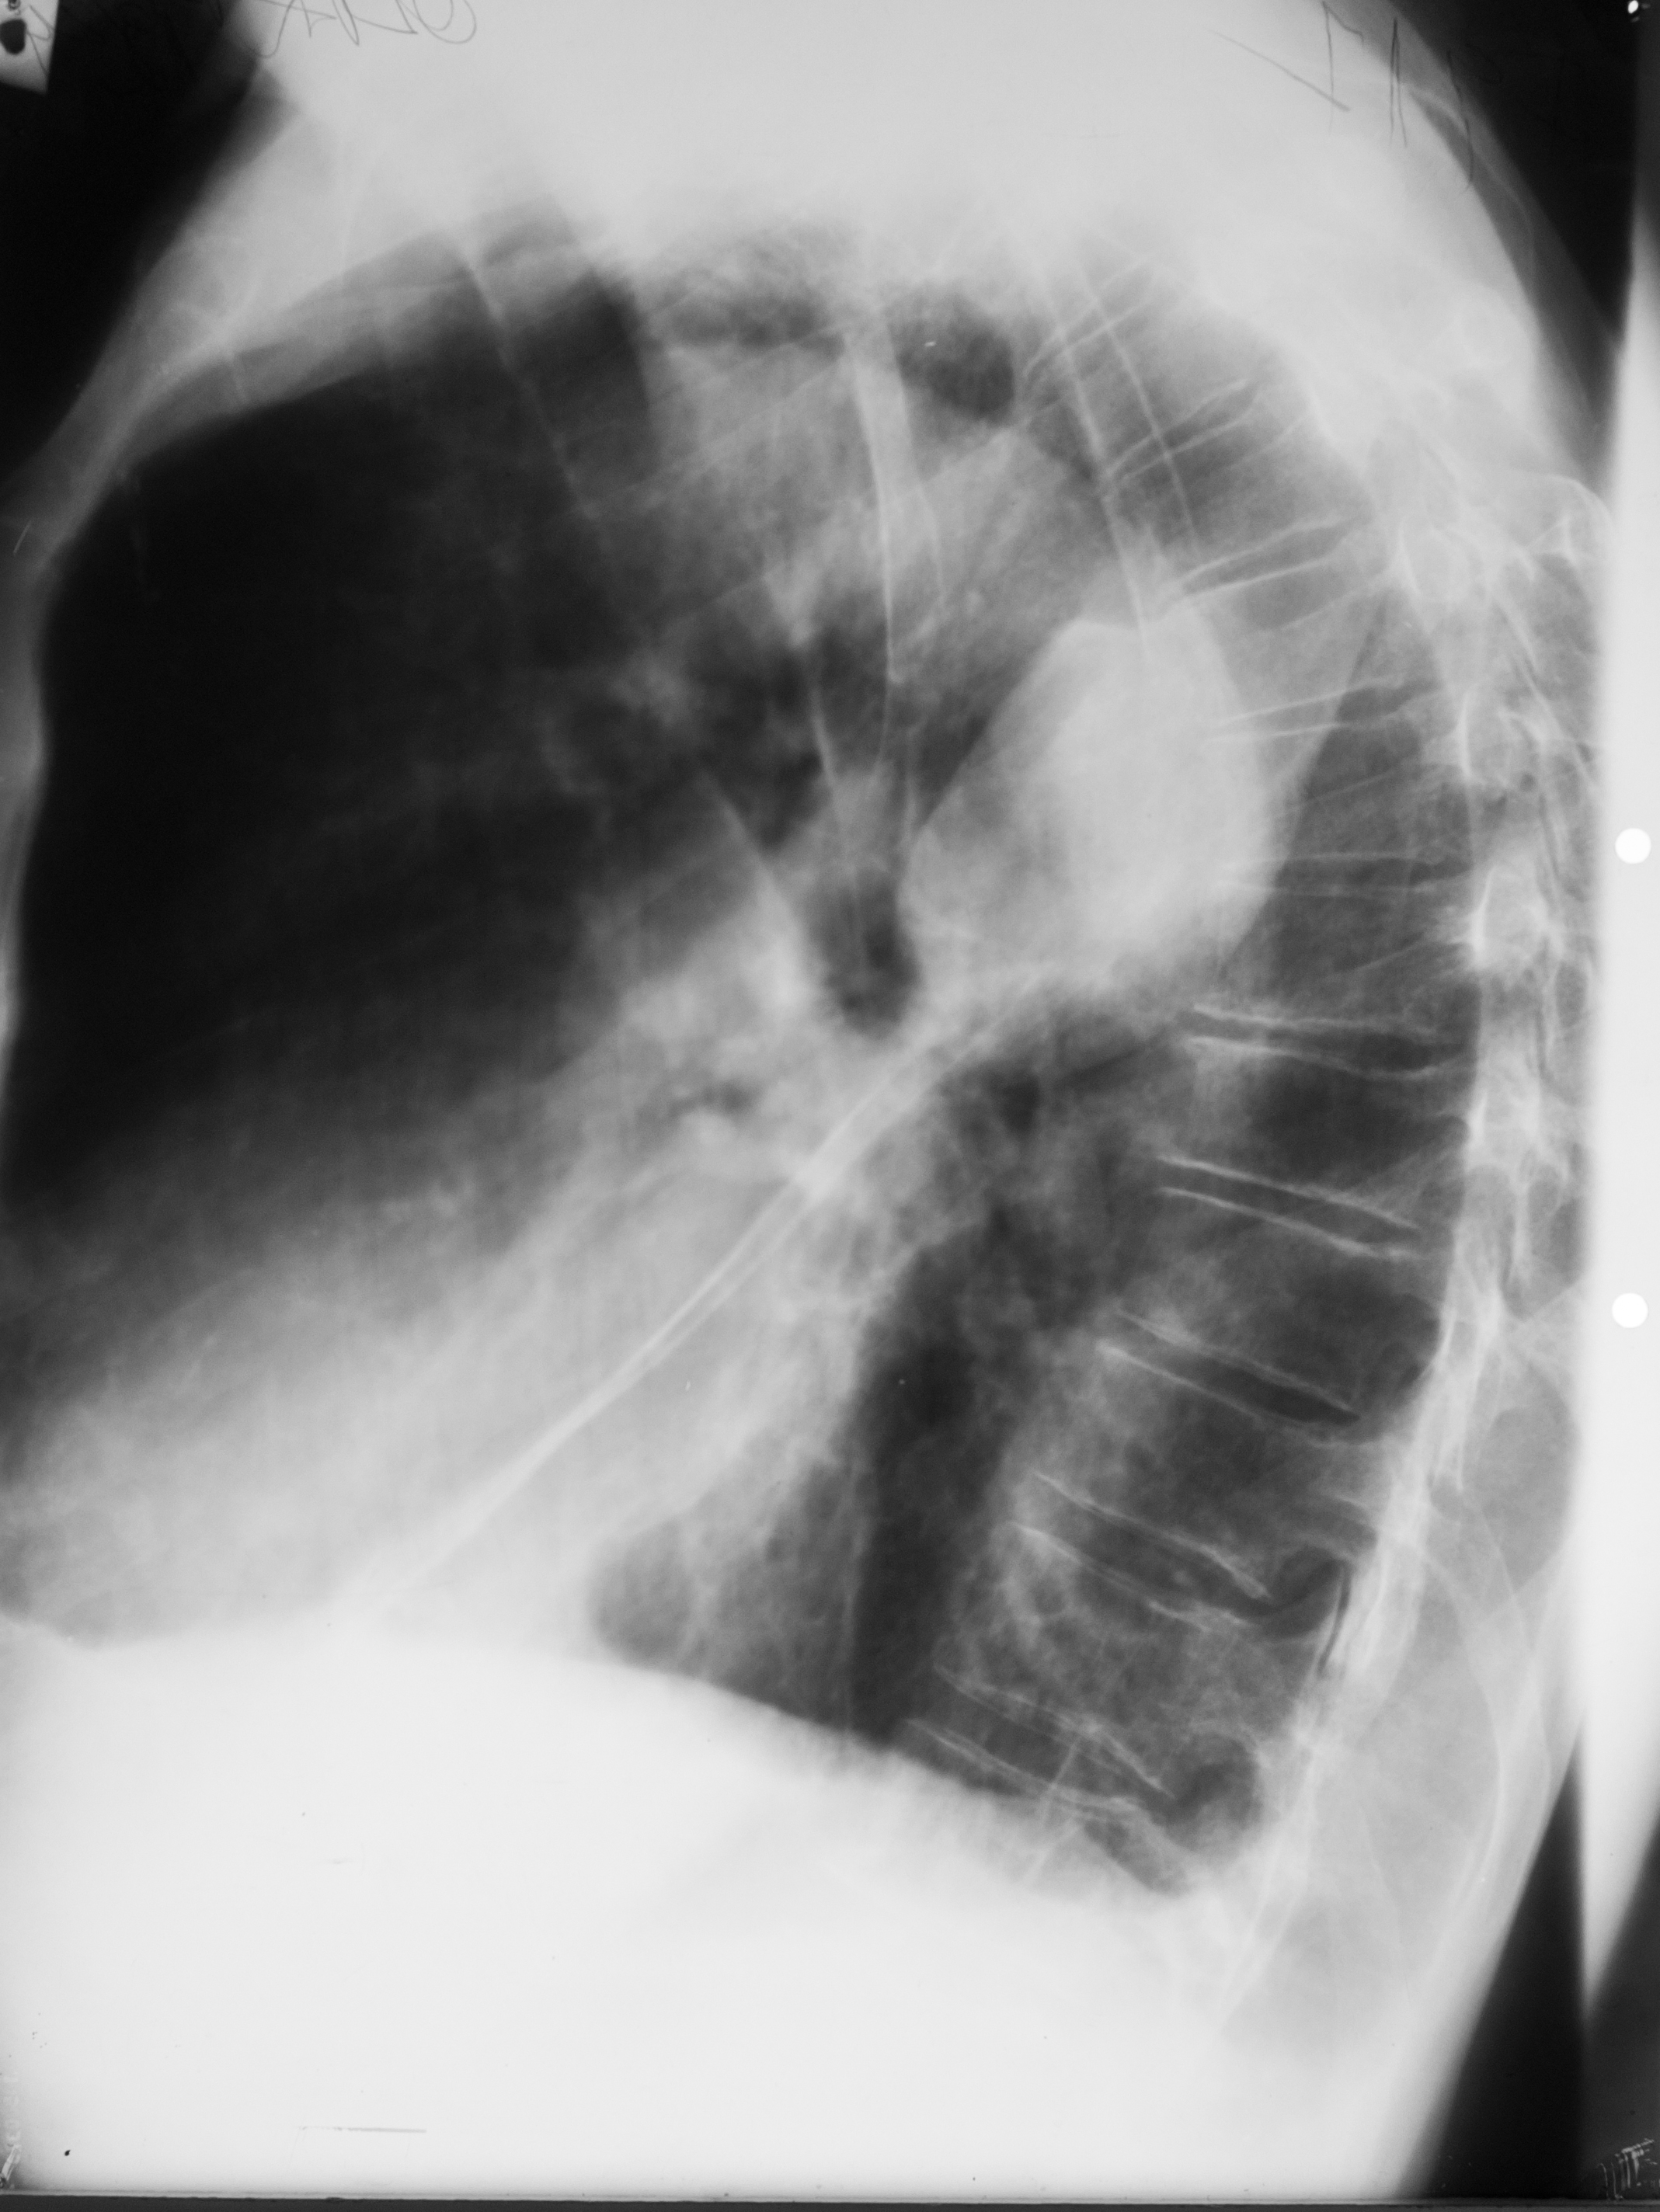

Rx toraco-mediastino-pleuro-pulmonar,de profil – opacitate

CHIST SUPRAINFECTAT VĂZUT DIN PROFIL (radiografie de profil)

Imagine hidroaerică,mixtă

ABCES PARȚIAL DETERJAT PE RADIOGRAFIA DE PROFIL